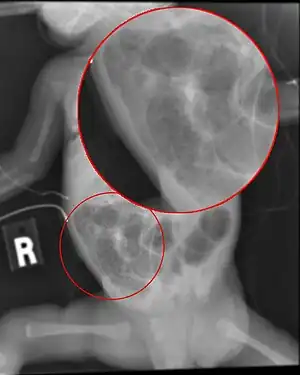

| Radiograph of a baby with necrotizing enterocolitis | |

The diagnosis is usually suspected clinically but often requires the aid of diagnostic imaging modalities, most commonly radiography. Specific radiographic signs of NEC are associated with specific Bell's stages of the disease:[6]

- Specific radiologic signs (pneumatosis intestinalis or portal venous gas

- Severe radiologic signs (pneumoperitoneum)